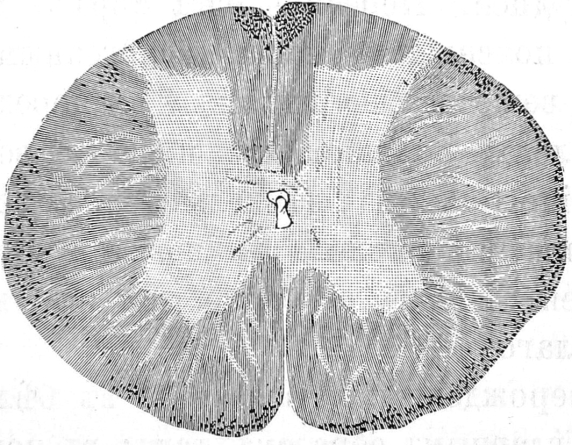

C. Spronck 25) въ своей работѣ: „Contribution а l'etude experimentale des lesions de la moelle épiniere determinées par l’anemie passagére de cet organe", вполнѣ подтверждаетъ опыты Ehrlich’a и Brieger’a и описываетъ наблюдавшіяся измѣненія въ спинномъ мозгу: нервныя волокна сѣраго вещества, за исключеніемъ заднихъ корешковыхъ волоконъ и центральныхъ волоконъ переднихъ и боковыхъ столбовъ перерождаются, Дейтерсовы отростки гангліозныхъ клѣтокъ переднихъ роговъ отдѣляются отъ послѣднихъ и распадаются на 4-й день. Распадъ мякотныхъ волоконъ обыкновенно сопровождается варикозной гипертрофіей осевыхъ цилиндровъ.

Уже 10-минутная задержка крови, по словамъ C.Spronck а достаточна, чтобы вызвать патологическія измѣненія въ поясничной части спинного мозга.